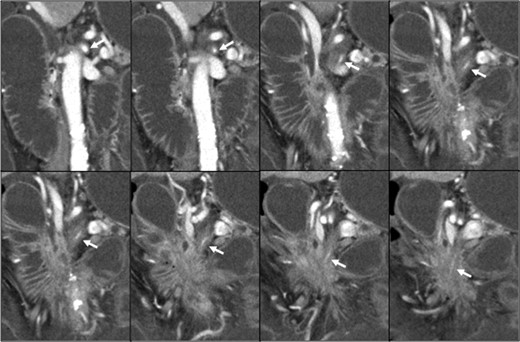

Pancreatic head cancer invaded the whole circumference of the SMA (white arrow), and the SMA showed stenosis and occlusion.